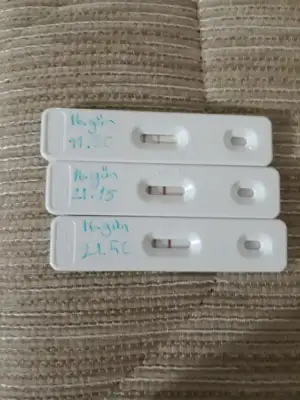

daha bunu dogurmadan bidaha Dogurasım geldi

Vallahi sen adamı dogurmaya özendiriyorsun kızÖyle bi yaşarsın ki allahım bu zmn nasıl geçti diyeceksin. Ben ilk kızıma hamileyken daha ilk ya karnında bebek olduğuna bile inanmıyorsun annelik duygusu yoktu bile. Yeğenlerime bakıyordum ya acaba benim karnımdaki de bunlar gibi gülüp oynayacak mı. Acaba ağzı kulağı gözü varmı benle konuşacak mı acaba. Acaba karnımdaki bir insan mı diyordumbi ultrason fotoğrafında değişikti insana benzemiyordu ablam baktı aa bu ne kız ne var senin karnında maymun mu doğuracan dedi ben artık karnımda bebek olduğuna zor ikna oldum. Çünkü gerçek gibi gelmiyor hiçbirşey. hamilesin ama annelik duygusu olmayınca insan bi tuhaf oluyor

ilk kızım doğduktan 3 ay sonra tekrar hamile kaldım. Şimdi biri bir buçuk diğeri iki buçuk yaşında